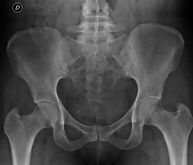

Procediment que permet, mitjançant l'ús de raigs X, i després d'injectar un contrast a l'interior de l'articulació, detectar lesions d'aquestes articulacions (cartílag, os, tendons, etc. ) segons la distribució del contrast. - RX Pelvis

Procediment que usa els raigs X a través de la qual s'obtenen imatges de la pelvis per al seu estudi, especialment dels ossos pèlvics. - RX Edat òssia

Estudi que usa els raigs X a través de la qual s'obtenen imatges del maluc i permet descartar luxacions. - RX Seriada òssia

Tècnica que usa els raigs X a través de la qual s'obtenen imatges d'ambdues extremitats per al seu estudi. - RX Malucs

Estudi que utilitza els raigs X per obtenir una imatge dels ossos de maluc i descartar luxacions. - Cistografia